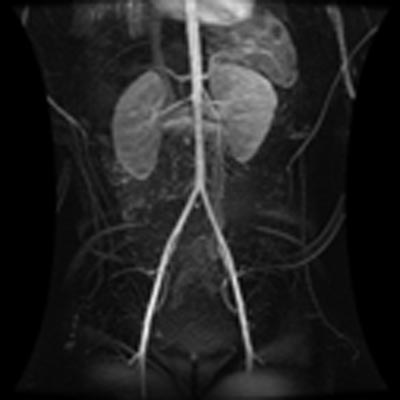

This image shows a magnetic resonance angiogram of the abdominal and pelvic vessels of a child. For more information see MR Angiography (MRA).

Note: Images are shown for illustrative purposes. Do not attempt to draw conclusions or make diagnoses by comparing these images to other medical images, particularly your own. Only qualified physicians should interpret images; the radiologist is the physician expert trained in medical imaging.